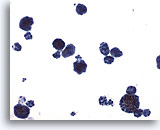

Peritoneal effusion: Metastatic carcinoma of the breast. Note malignant cells contrasting with benign histiocytes. Note large intracytoplasmic vacuoles with mucin droplets. 60X

Peritoneal effusion:

Metastatic carcinoma of the breast. Note malignant cells contrasting with benign histiocytes. Note large intracytoplasmic vacuoles with mucin droplets.

60X